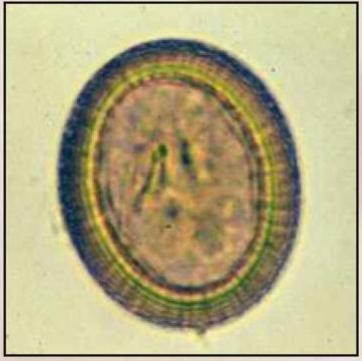

Mikroskopy w medycynie to specjalistyczne urządzenia optyczne służące do powiększania i szczegółowej obserwacji struktur niewidocznych gołym okiem, takich jak komórki, tkanki czy mikroorganizmy. Są stosowane w diagnostyce, badaniach laboratoryjnych, zabiegach chirurgicznych i nauce medycznej.

Celem ich użycia jest dokładna analiza mikroskopowa materiału biologicznego oraz wspomaganie precyzyjnych procedur medycznych.

• Badanie próbek krwi, moczu, płynów ustrojowych, wycinków tkanek (histologia) i mikroorganizmów (bakteriologia, wirusologia).

• Identyfikacja chorób zakaźnych, nowotworowych, hematologicznych.

• Stosowane w diagnostyce wirusów, bakterii i badań immunologicznych.

• diagnostyki laboratoryjnej (komórki, tkanki, mikroorganizmy),